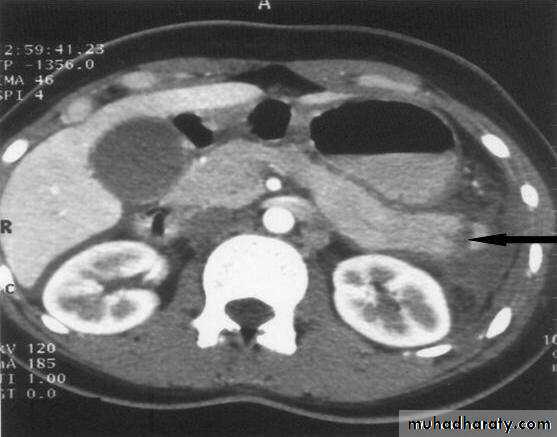

Radiology of acute pancreatitis

GIT

U/S 

useful for biliary pathology, 70-80% sensitive for pancreatitis

CT more useful for judging severity and regional effects

Try to wait >12 hours as early CT is usually unhelpful